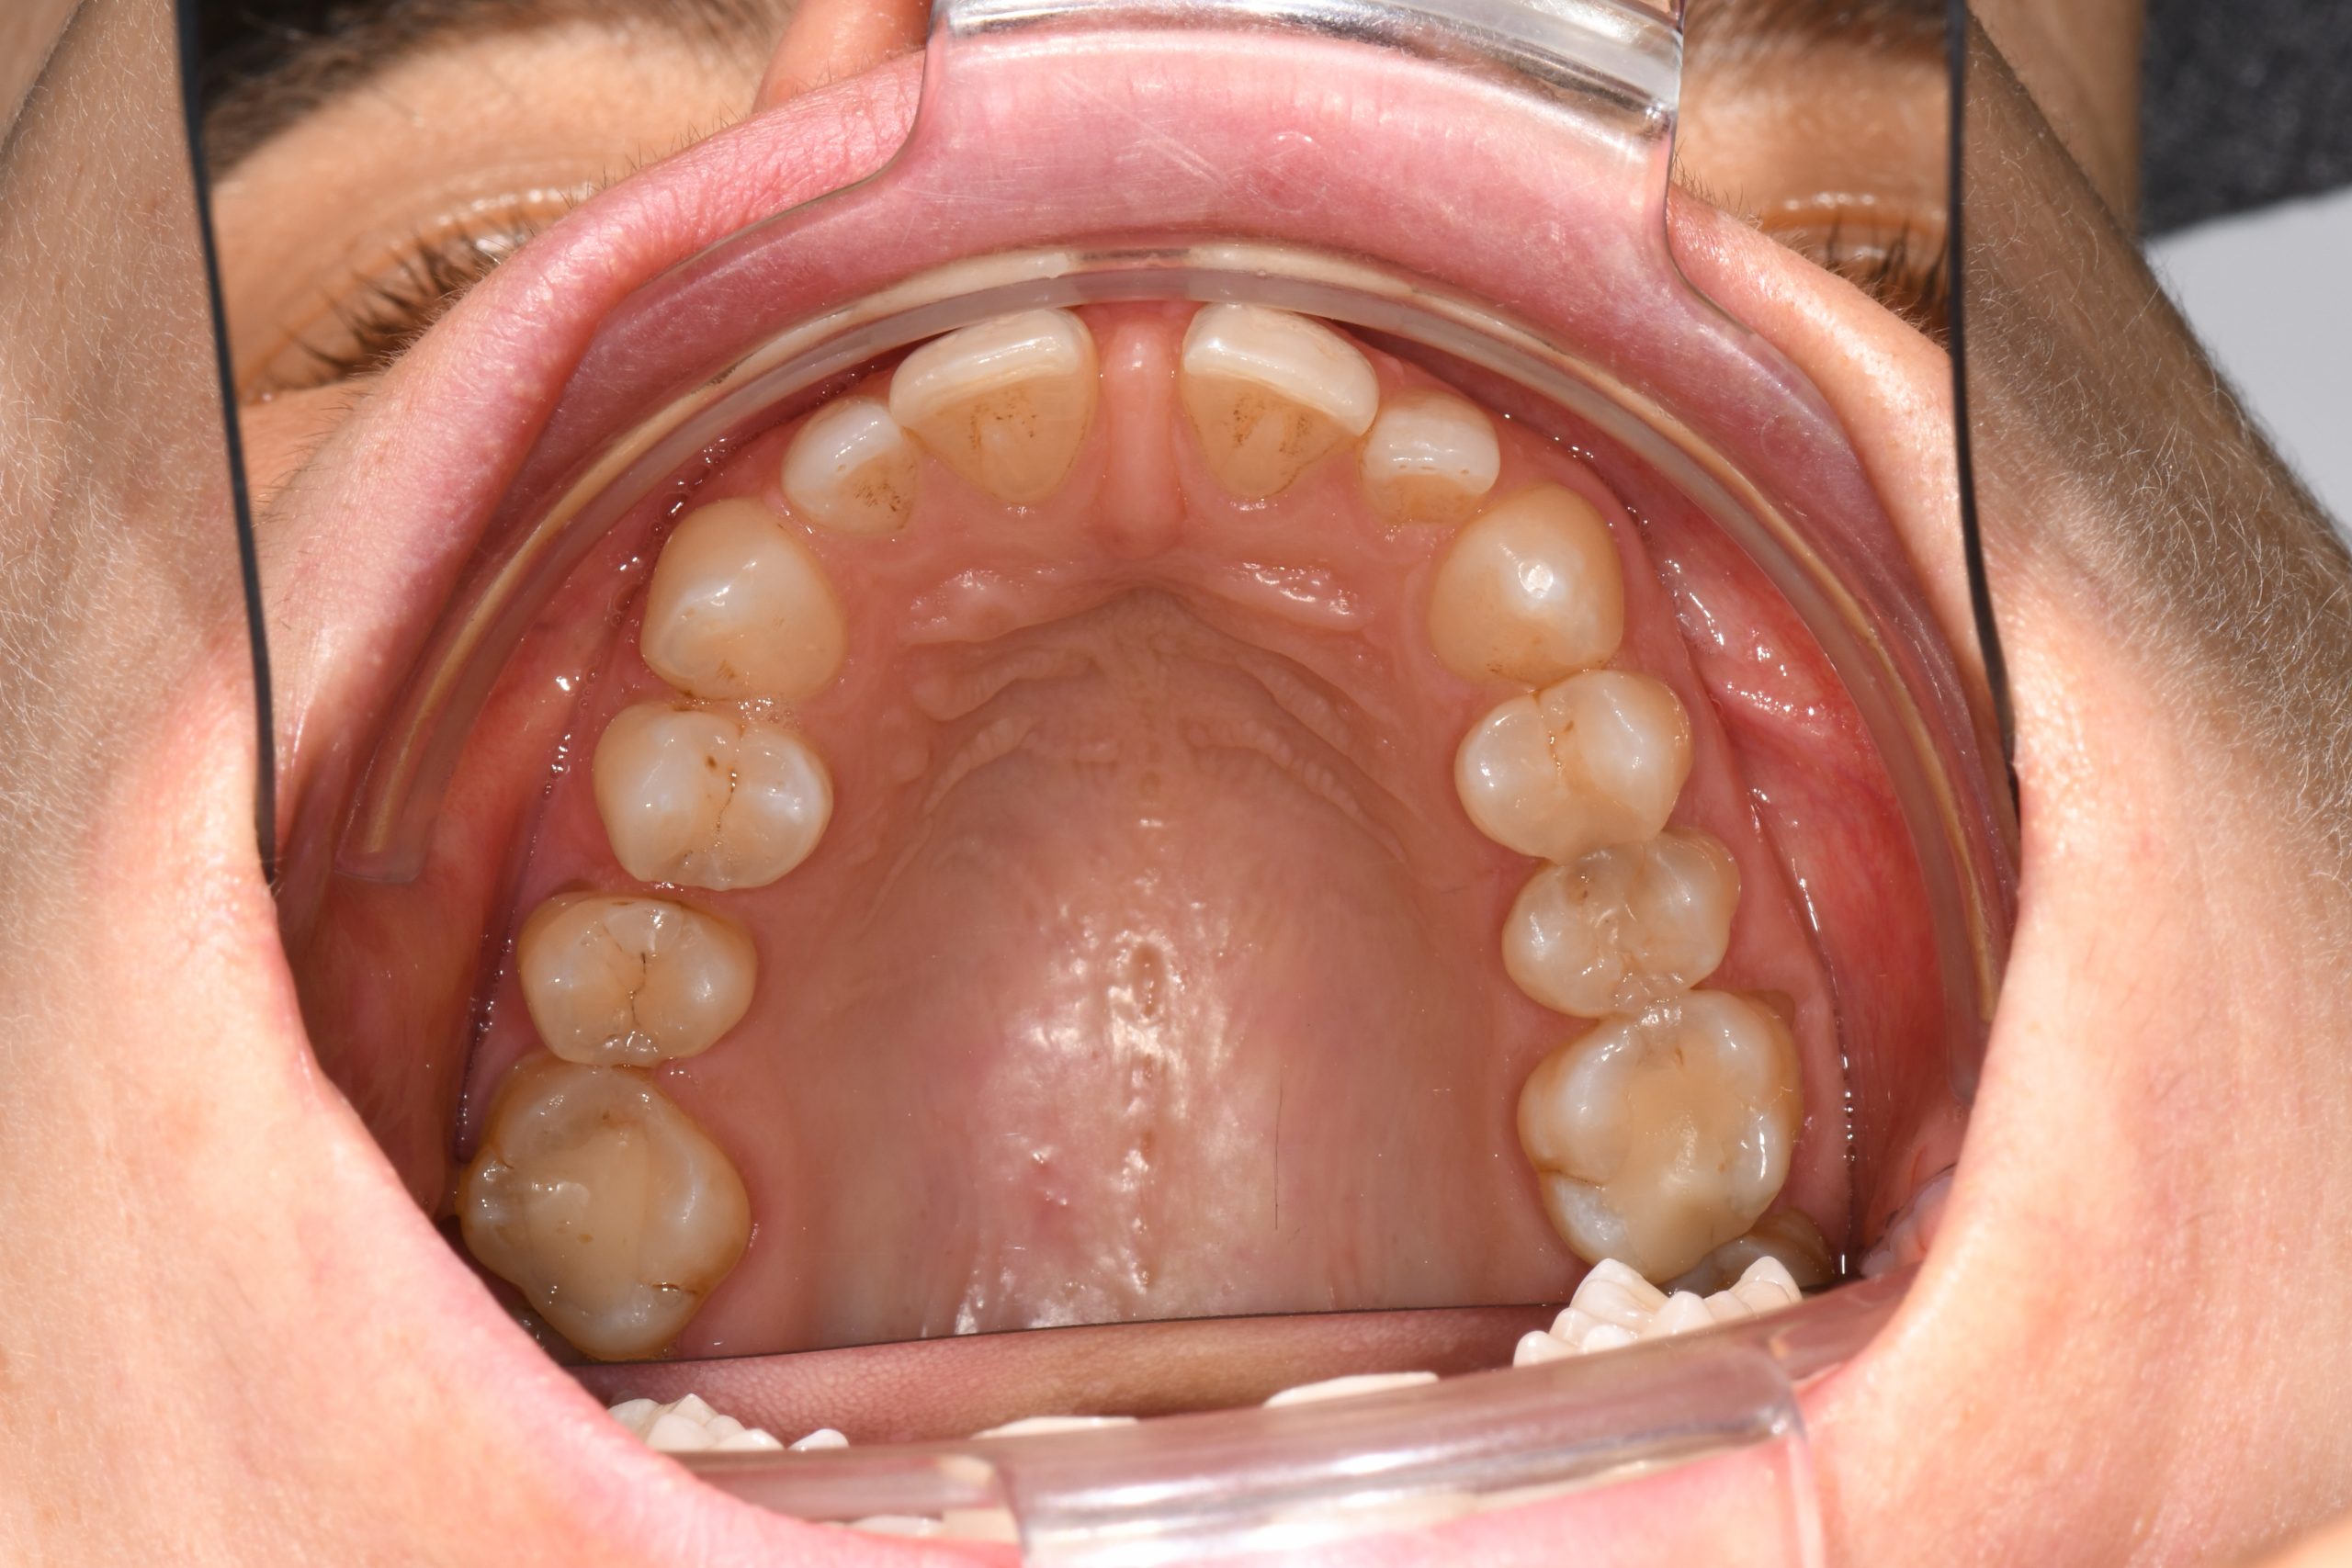

Az elmúlt évekből rengeteg szakmai referenciát tudnánk bemutatni, amelyek különböző fogszabályozási problémákat oldottak meg. Válogatva a több száz esetből, ezen az oldalon olyan képeket, információkat igyekeztünk bemutatni, amelyeknek a segítségével a jövőbeni pácienseinknek azt tudjuk üzenni: A Te fogsorod is lehet gyönyörű!